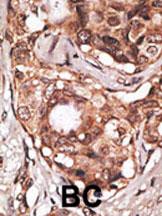

Formalin-fixed and paraffin-embedded human cancer tissue reacted with the primary antibody, which was peroxidase-conjugated to the secondary antibody, followed by DAB staining. This data demonstrates the use of this antibody for immunohistochemistry; clinical relevance has not been evaluated. BC = breast carcinoma; HC = hepatocarcinoma. |